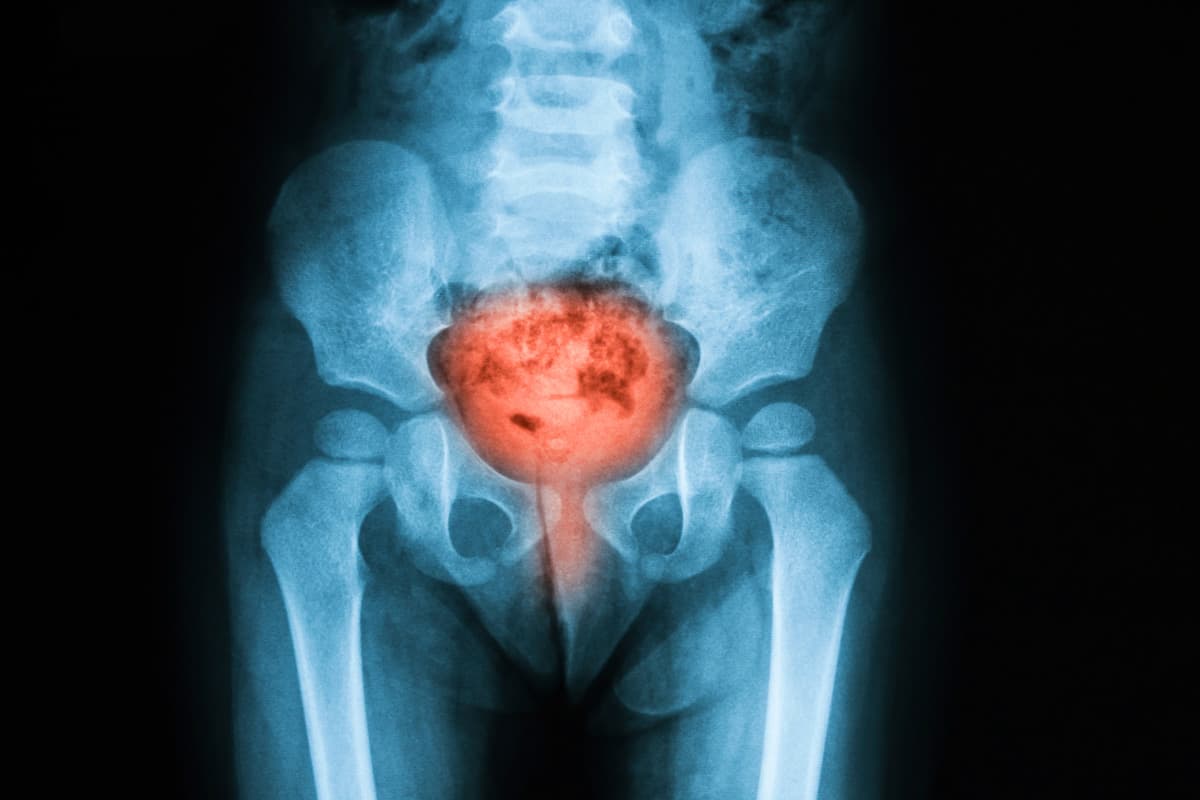

Urinary tract infections (UTIs) are infections that affect any part of the urinary system, including the kidneys, ureters, bladder, and urethra. Most commonly, UTIs involve the lower urinary tract, particularly the bladder (a condition known as cystitis) and the urethra (urethritis). They occur when microorganisms—usually bacteria—enter the urinary tract through the urethra and begin to multiply. The most frequent cause is Escherichia coli, a bacterium that normally lives in the digestive tract but can cause infection when it spreads to the urinary system. Symptoms of a UTI often include a strong and persistent urge to urinate, a burning sensation during urination, cloudy or strong-smelling urine, and pelvic discomfort. In more severe cases, particularly when the infection spreads to the kidneys (pyelonephritis), symptoms may include fever, chills, nausea, and lower back pain. UTIs are very common, especially among women, due to anatomical differences that make it easier for bacteria to reach the bladder. While most UTIs are easily treated with antibiotics, prompt diagnosis and treatment are important to prevent complications or the spread of infection to the upper urinary tract.

Urinary tract infections (UTIs) can cause a range of signs and symptoms depending on which part of the urinary system is affected. Infections of the lower urinary tract, particularly the bladder (cystitis), are the most common and often produce a strong, persistent urge to urinate along with a burning sensation during urination. People may notice passing small amounts of urine frequently, even when little comes out. Urine may appear cloudy, dark, or tinged with blood and can have a strong or unusual odor. Pelvic pressure or discomfort in the lower abdomen is also common, especially in women. When a UTI spreads to the kidneys (pyelonephritis), symptoms can become more severe and may include high fever, chills, nausea, vomiting, and pain in the lower back or side beneath the ribs. Some individuals, particularly older adults, may experience more subtle symptoms such as confusion, fatigue, or general weakness rather than the typical urinary complaints. Children may develop fever, irritability, or feeding difficulties. Because symptoms can vary in intensity and presentation, recognizing changes in urination patterns or unexplained discomfort is important. Prompt medical evaluation and treatment can help relieve symptoms quickly and prevent the infection from progressing to more serious complications.